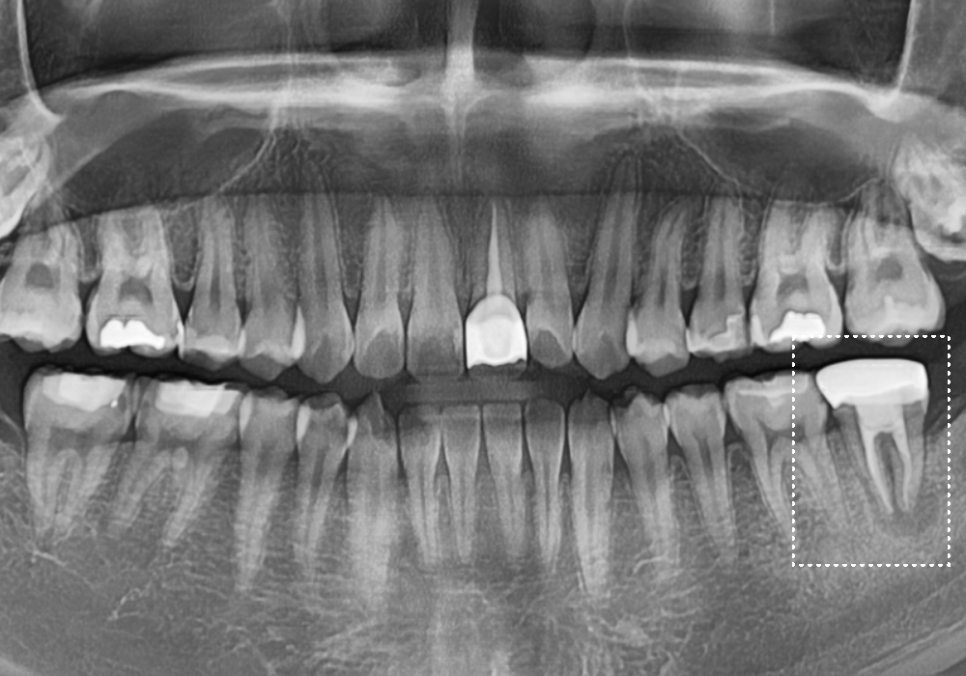

얼마 전 1년 전 신경치료를 받았던

오른쪽 아래 어금니(#37) 문제로

한 환자분이 내원하셨어요.

뿌리 염증 때문에 타병원에서

발치 후 임플란트 권유 받으셨다고 하는데,,

환자분이 아직 너무 젊으셨어요.

임플란트하기엔 너무 아까운 나이.. ㅠㅠ